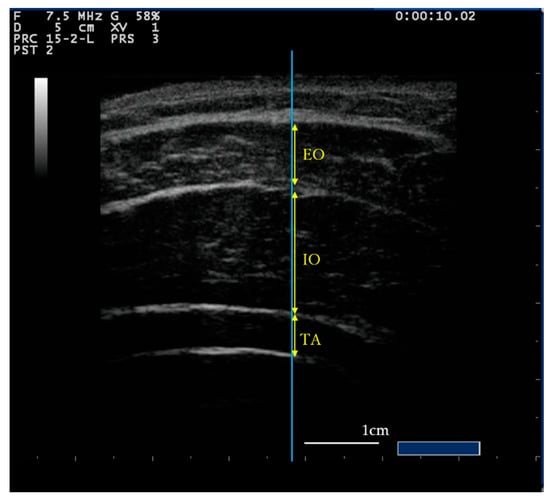

2.3. Measurement Procedure